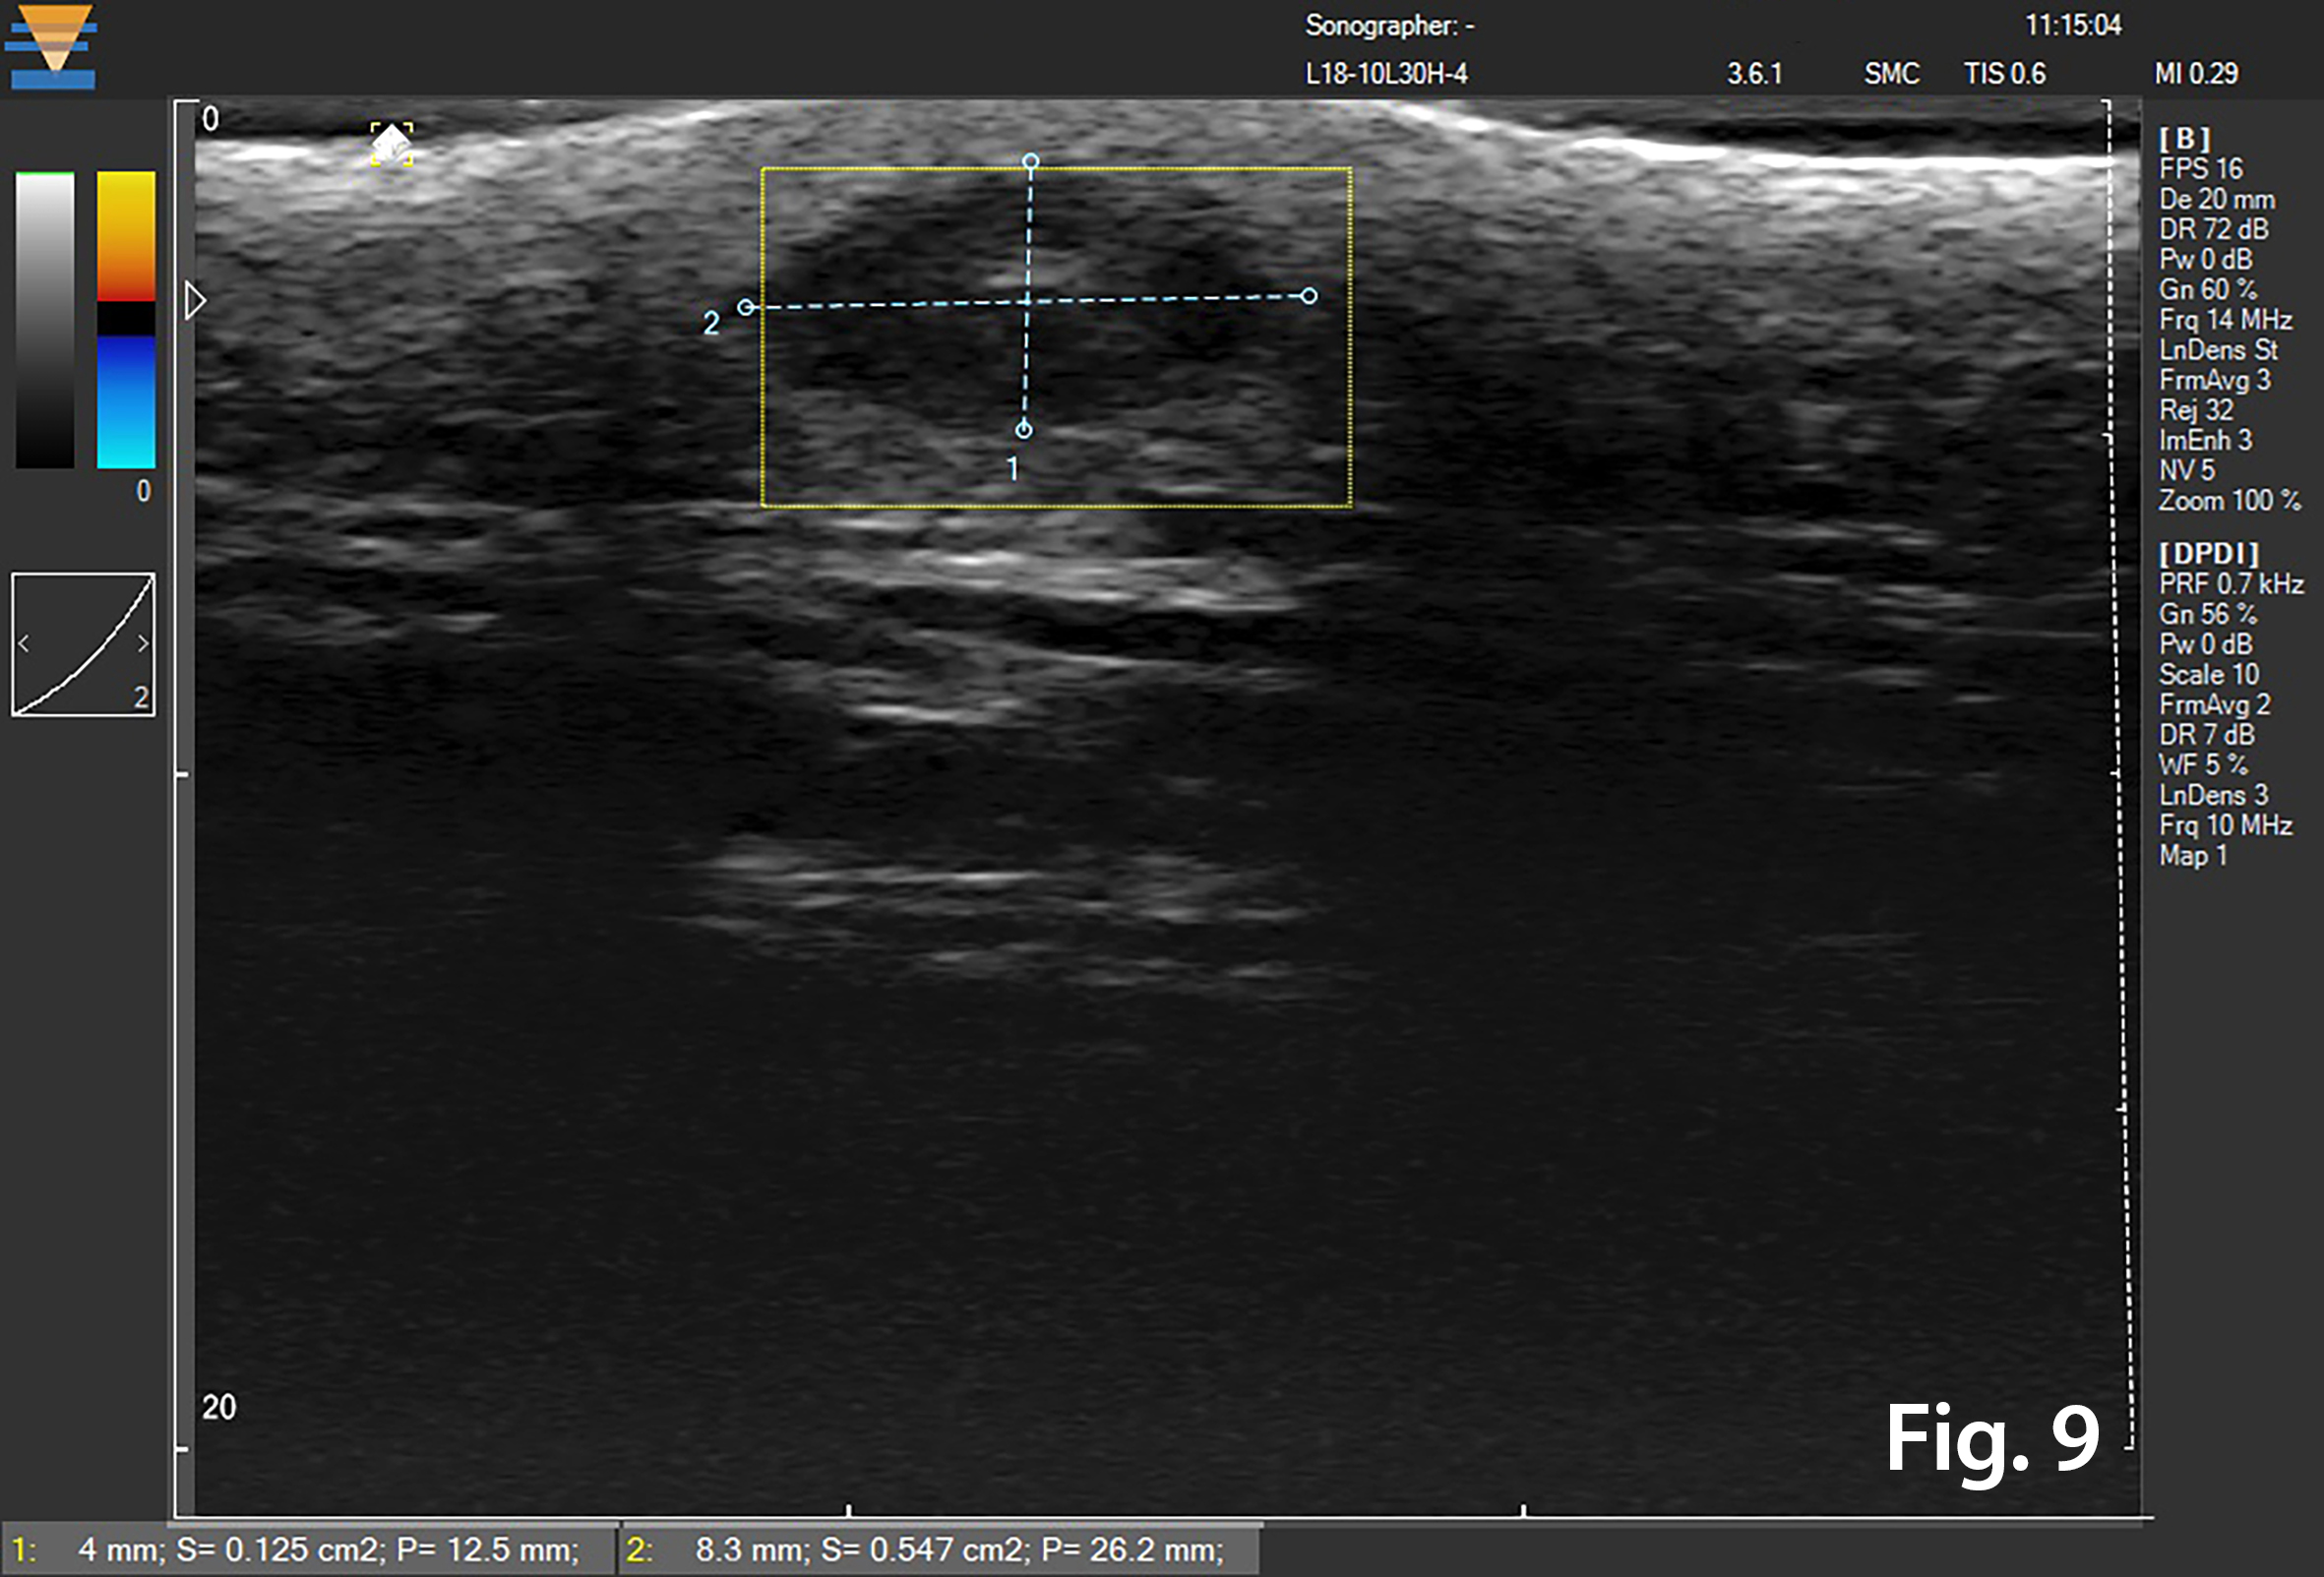

18 MHz ultrasound examination in B Mode and Colour and Power Doppler of the adjacent pigmented skin area on the left side of the melanocytic lesion revealed that the hypo-heteroechoic area 8.3x4.0 mm, was located in the lower part of the dermis within subcutaneous fat, and demonstrated posterior acoustic enhancement. The central part of the lesion was hyperechoic and it had a heteroechoic periphery. There was no intra-lesional blood flow.

Figure 9. 18 MHz image in B-Mode and Colour and Power Doppler Mode of the adjacent to the nevus pigmented skin area. The hypo-heteroechoic area 8.2 x 4.2 mm is located in the lower part of the dermis and in subcutaneous fat, with posterior acoustic enhancement. The central part of the lesion is hyperechoic with heteroechoic periphery. There was no intra-lesional blood flow.